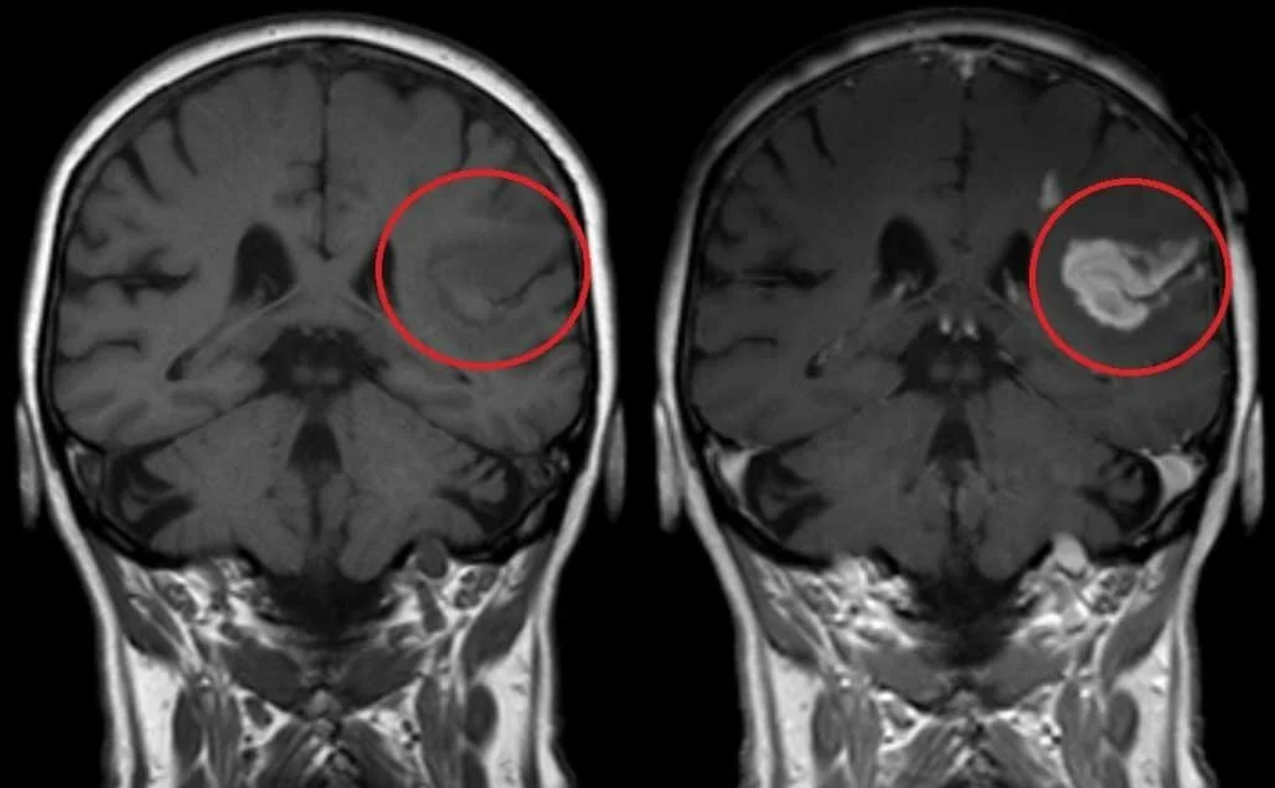

Демиелинизирующие заболевания мозга: МРТ изображения